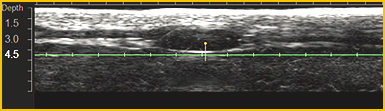

通过已获得专利的超声波影像技术,施术院长可以直接通过肉眼确认患密集的皮肤状态.

同时可避开骨骼及血管等敏感位置,将痛症和淤青降低到最小化.

施术时可通过实时超声波影像,确定骨骼和血管位置,可避免浮肿、痛症最小化.